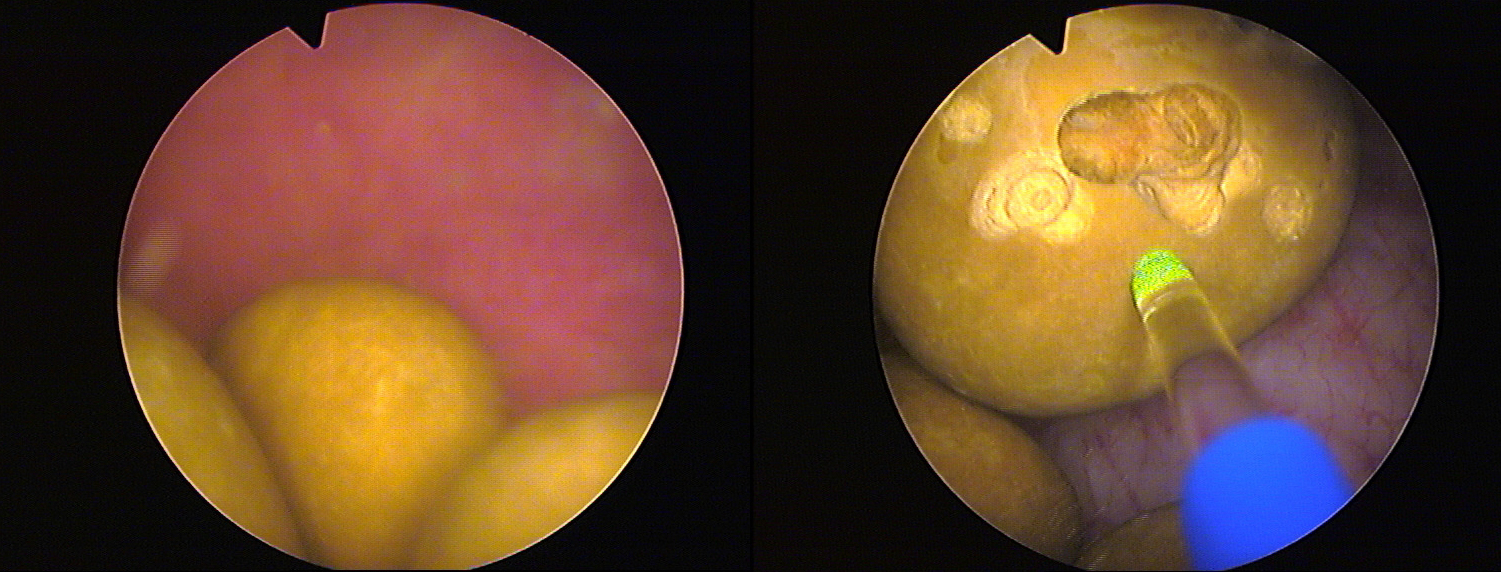

Die Klinik geht seit einigen Jahren einen anderen Weg: Statt der klassischen OP nutzt sie einen sogenannten Holmium-YAG-Laser des deutschen Herstellers Wolf aus dem schwäbischen Knittlingen zur Therapie. Die Faser eines 'MegaPuls 30+'-Lasers wird mittels Zystoskop, einem Instrument zur Blasenspiegelung, über die Harnröhre in die Blase geleitet und zerstört dort mit gepulsten Energiestößen von 200 bis 4000 Millijoule (mJ) die Blasensteine. "Wir durchfahren während der Behandlung ein Impuls-Spektrum von 3 bis 25 Hertz, da jeder Stein anders aufgebaut ist und jeder Stein bei einer anderen Impulsfolge zerplatzt", beschreibt der Martin Löhr das Verfahren. Jeder Puls ist dabei mit 150 bis 850 Mikrosekunden (µs, Millionstel Sekunde) extrem kurz. Der Stein-Laser bringt dabei eine Leistung von 30 Watt. Er arbeitet zwar auch mit einem grünen 532-Nanometer-Laserstrahl, doch dieser gilt nur als Orientierung für den Operateur; er ist quasi ein Pilotstrahl. Der eigentliche Impuls zur Zerstörung der Blasensteine kommt durch einen für das menschliche Auge unsichtbaren 2100-Nanometer-Laserstrahl.

Je nach Zahl und Größe der Blasensteine dauert eine Laser-Behandlung zwischen wenigen Minuten und einer Stunde. Da sich der Patient in einer leichten Narkose befindet, spürt er von alledem nichts.